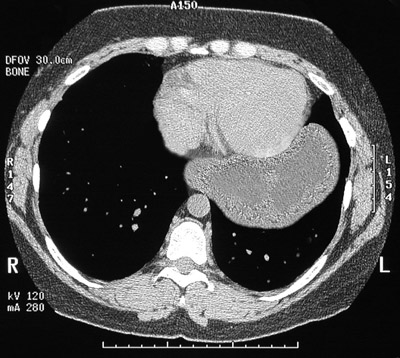

![]() | This chest CT scan reveals that much of the stomach is seen in the left chest cavity adjacent to the heart. This complication is known as a paraesophageal hernia. The gastric wall is thickened from edema with early infarction from a compromised blood supply with constriction of the arterial supply through the narrow opening to the chest from the upper abdomen through the diaphragm. |